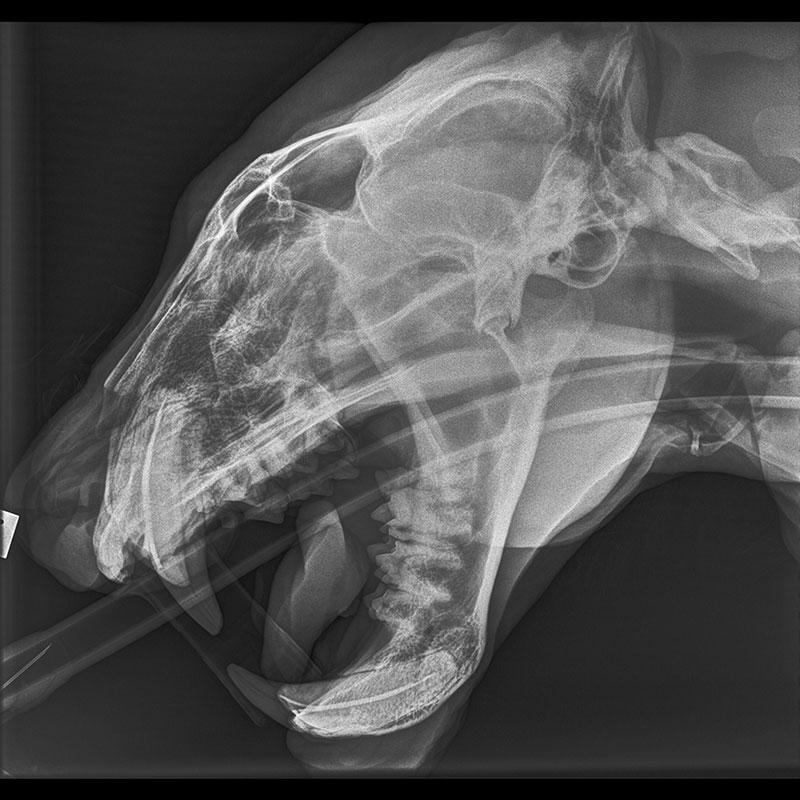

ภาพเอกซเรย์กะโหลกศีรษะของเจ้า “โรกัน” เสือตัวผู้หนัก 120 กก. ดาราของสวนสัตว์เวลลิงตัน กว่าจะจับมันถ่ายเอกซเรย์ได้ ต้องวางยาให้มันสลบเสียก่อน   หลังจากที่พนักงานรู้สึกว่าเสือหนุ่มอายุ 17 ปี ดูท่าว่าไม่ค่อยสบาย.